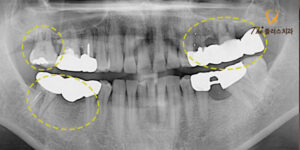

위 환자분은 40대 남성분으로,

상악 좌측 보철물로 씌워진 곳에 구멍이 나서

타 치과에서 떼웠었는데 계속 떨어지기를

반복하여 치과에 오게 되었다고 하셨는데요.

불편하다고 호소하신 보철물은

작은 어금니와 맨 뒤에 위치한 대구치의 빈자리를

수복하기 위해 4개의 치아를 브릿지로 제작한 상태였는데요.

소구치 자리의 크라운에는 구멍이 나있고,

과거 사용하던 캔틸레버 방식의 브릿지였습니다.

환자분께서도 대구치에 받는 힘이 강해

지대치의 치조골이 퇴축되면서 치아를

단단히 지지하지 못하고 있었으며,

구멍이 난 소구치도 치아 내부로 2차 우식이

진행되어 있는 상태였습니다.

또한 반대쪽 맨 안쪽에 위치한

대구치도 흔들림이 심하다고 하셨는데요.

파노라마 상으로 보기에도 치아를

지지해주는 치조골이 대부분 녹아 있는 상태였으며,

금으로 씌워져 있는 소구치에도 염증이 발생되어 있었습니다.